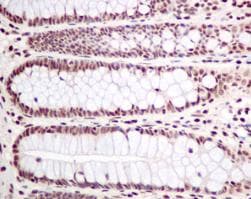

Rabbit Recombinant Monoclonal PLK1 phospho T210 antibody. Carrier free. Suitable for Dot, WB, IHC-P and reacts with Human, Mouse samples.

Applications Dot, IHC-P, WB

Species Reactivity Human, Mouse